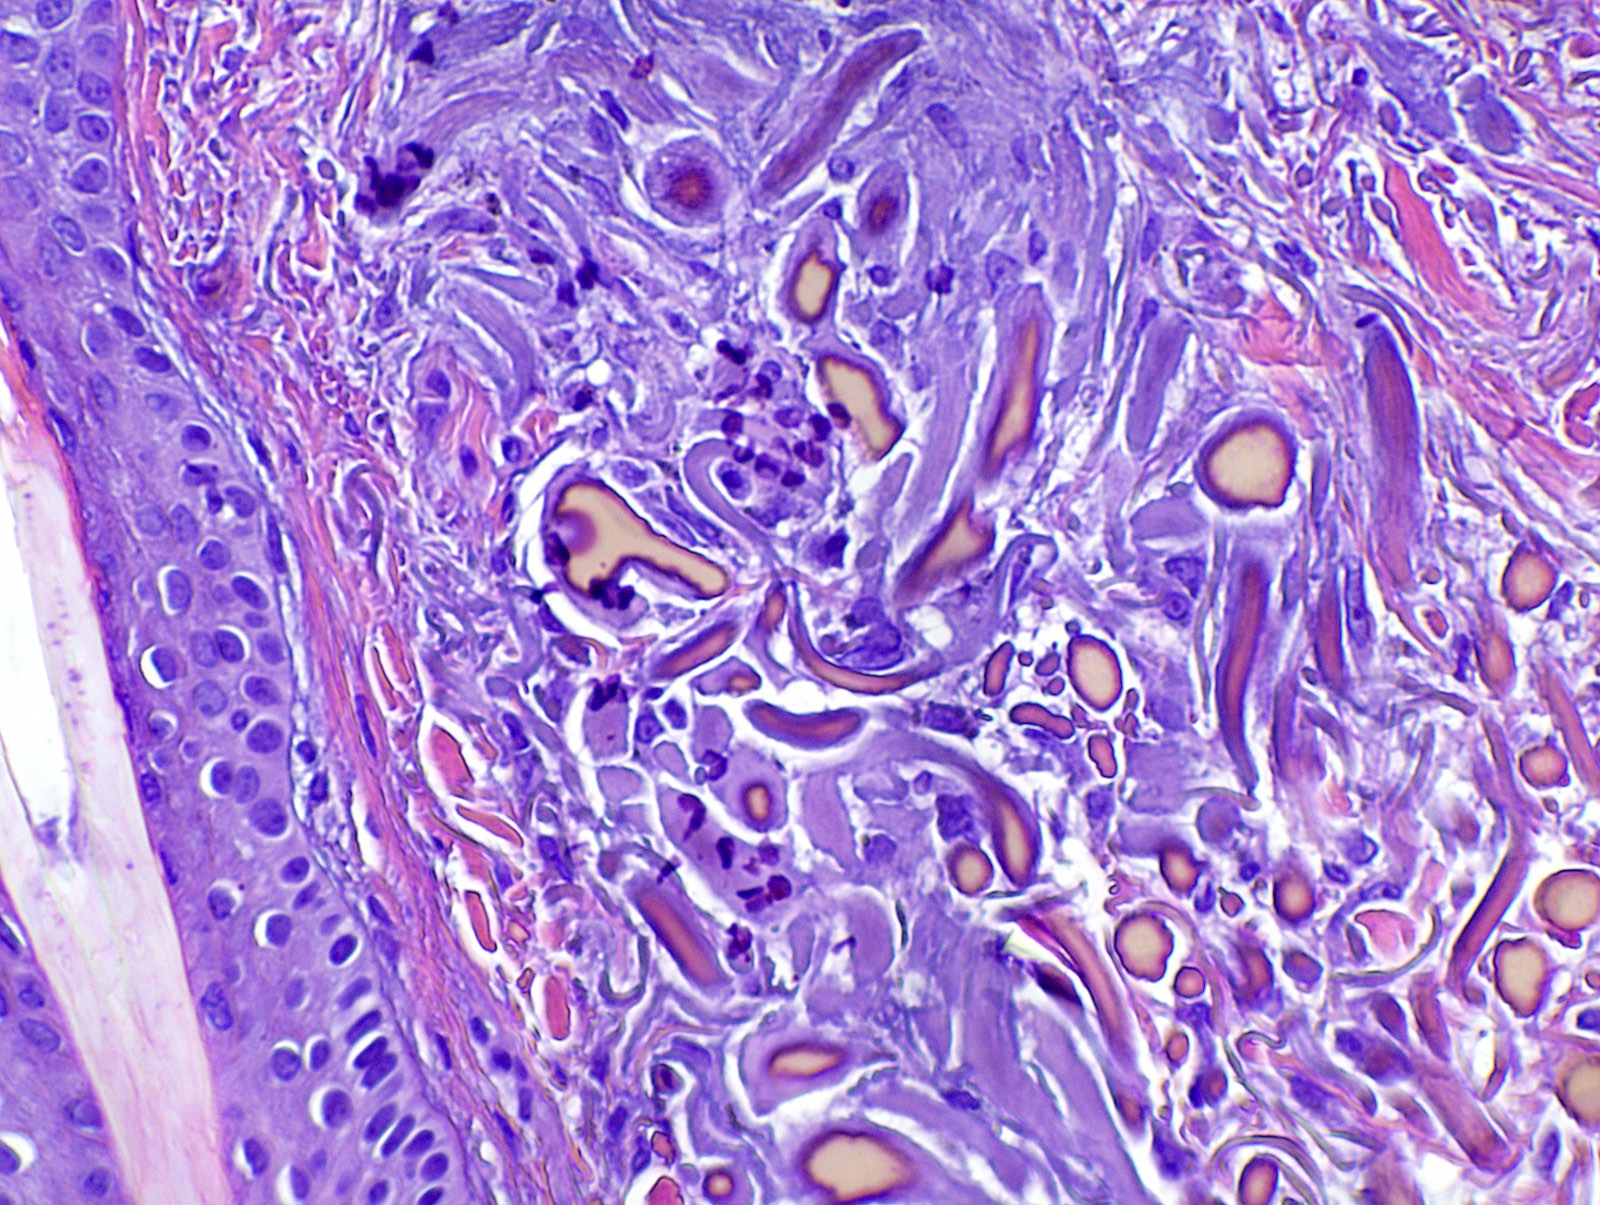

Still's Disease Dermatopathology Still's Disease Dermatopathology It is important to be aware of the broad histologic spectrum that may be encountered in still disease. Arthritis (joint pain and swelling) high spiking fevers once or twice daily. Still's Disease Dermatopathology.